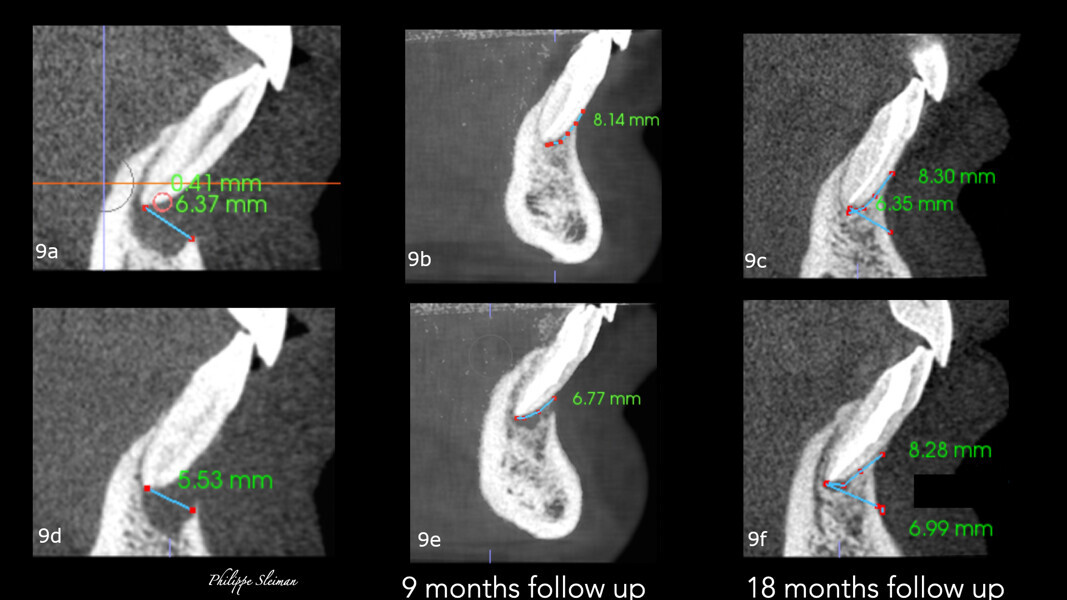

A comparison of the i-CAT scans taken preoperatively and at the nine-month and 18 month follow-ups showed complete regeneration of the cortical and trabecular bone in great biological detail, showing even the groove of the frenum (Figs. 7 & 8). The bone view clearly showed the preoperative major horizontal and vertical bone defect and open periodontal defect, the beautifully regenerated, natural looking bone and the emergence of the mandibular nerve. Happily, the bone continued growing vertically (Fig. 9).

Figs. 9a–f: Comparison of the vertical views of the i-CAT scans taken pre-op (a & b) and at the nine-month follow-up (c & d) and 18-month follow-up (e & f), showing continued growth of the bone vertically.